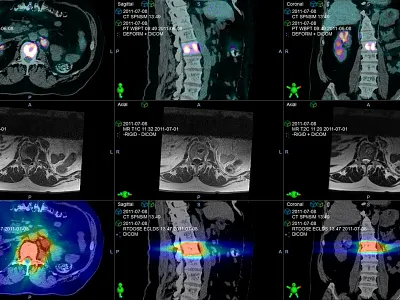

Imaging Software for Radiotherapy

Software and AI-based solutions tailored to your radiation therapy needs.

Velocity

Transform disconnected data into actionable clinical knowledge.